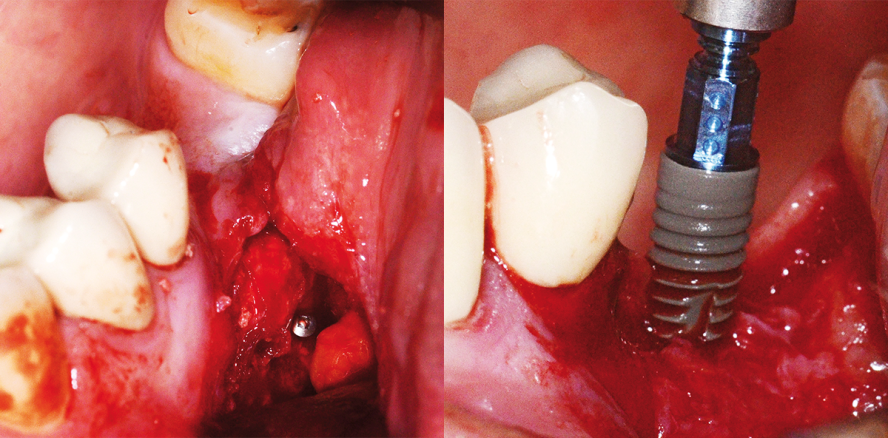

Nach dem Verlust von Frontzähnen kommt es rasch zu einem Verlust von Alveolarknochen, insbesondere in vertikaler und sagittaler Richtung.30,31 Wobei es zunächst aufgrund der dünnen, vestibulären Knochenlamelle zu ante­rioren Knochenresorptionen kommt, die später in vertikale Verluste übergehen. Es ist in einem Großteil der Fälle eine Knochenaugmentation nötig, wenn eine sinnvolle Sofortimplantation versäumt wurde.31,32 Eine sinnvoll geplante Sofortimplantation ist vorzuziehen. Anatoforme Implantat­designs können diesen Ansatz optimieren. Es ist auch ein Sofortbelastungskonzept möglich (Abb. 3).32–36 Ergebnisse, welche diesen Daten entgegen stehen, müssen auch in Bezug auf Implantatdesign und Biomaterialoberflächen diskutiert werden.37–39 In der Unterkieferfront und in den Bereichen der lateralen Oberkieferschneidezähne sind Niederquerschnitts­implantate mit einem Durchmesser von 3 mm oder darunter indiziert und für eine Einzelkronenversorgung eine mögliche Option (Abb. 4).

Im Falle eines echten absoluten Alveolarkammhöhenverlustes kann eine vertikale Knochenaugmentation oder bei großen seitlichen Defekten eine Lateral-Ridge-Augmentation indiziert sein. Für kleinere komplexe Defekte kann, ggf. auch mit simultaner Implantation, eine Schalentechnik mit PTFE-Membran erfolgen (Abb. 6). Bei mittleren und großen vertikalen Defekten, insbesondere mit Freiendsituation, ist eine autologe Schalentechnik sinnvoll (Abb. 7 und 8). 3-D-Schalentechniken sind vorteilhaft und verkürzen die OP-Zeiten bei besserer Passung (Abb. 9).4 Diese komplexe und schwierige Indikation bedarf umfangreicherer Ausführungen an anderer Stelle.